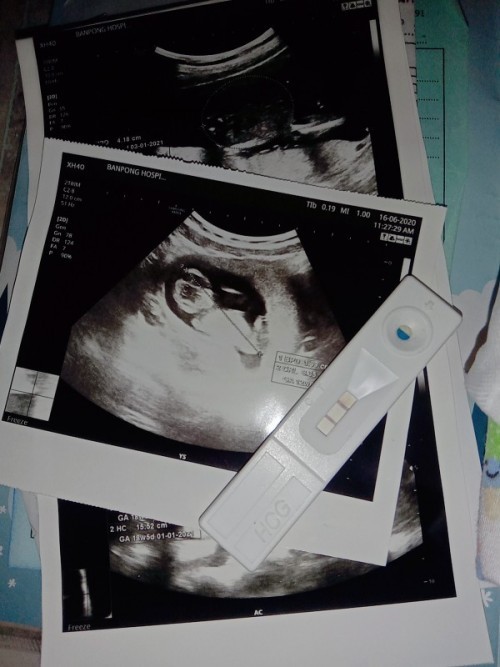

แม่! 🤰💖อวดรูปอัลตร้าซาวด์กัน

โชว์รูปแรกของเบบี้กันหน่อยน้า เพศหญิง👧หรือชาย🧑เอ่ยยย 😍🥰💜 17/09/2563

ตอนซาว ได้13วีคคะ ตอนนี้16วีคแล้ว